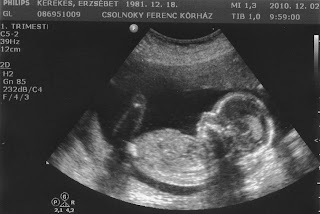

Túl a 18. héten. Legalábbis a naptár szerint. Az e heti kórházas UH szerint ugyanis a méreteik alapján "még csak" 17 és fél hetesek. De ne rohanjunk ennyire előre...